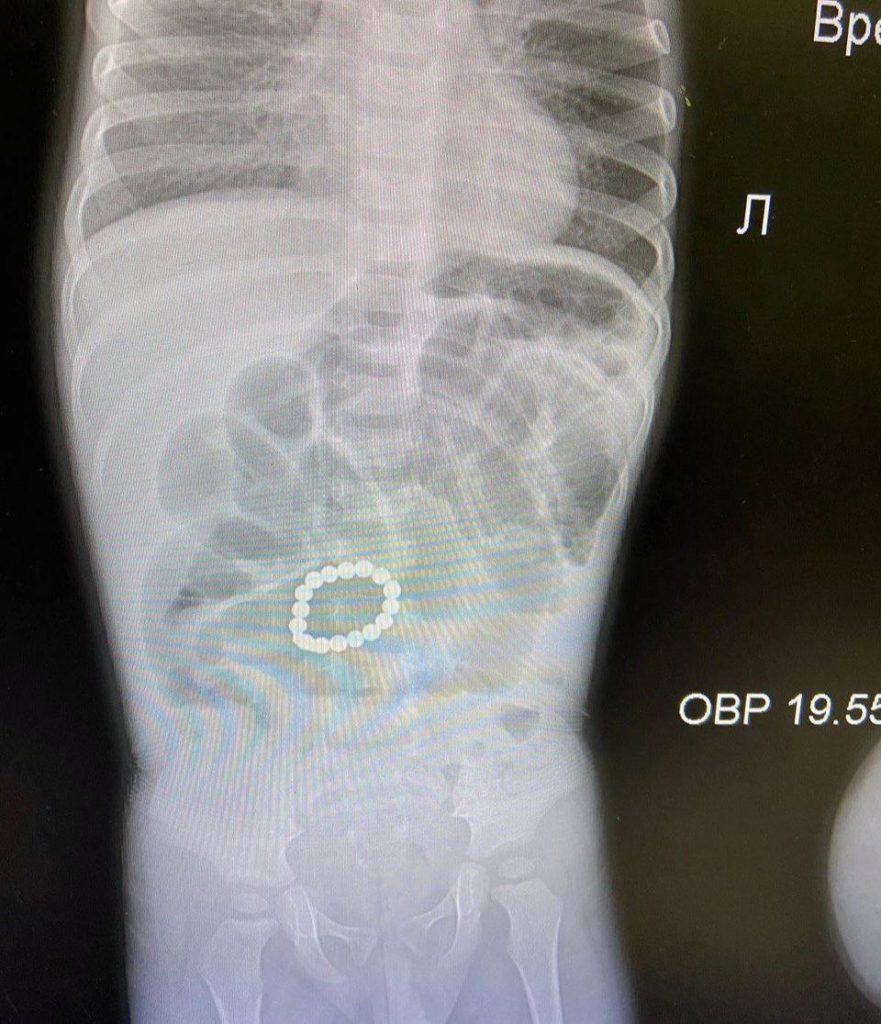

В инфекционное отделение Раменской больницы бригадой скорой медицинской помощи был доставлен ребенок в тяжелом состоянии. У полутарогодовалого малыша отмечалась высокая температура, сильное вздутие живота, выраженная слабость и ребенок отказывался есть. Только благодаря проведению обзорной рентгенографии органов брюшной полости удалось распознать в организме 15 штук металлической мелочи. Операция была выполнена в экстренном порядке.